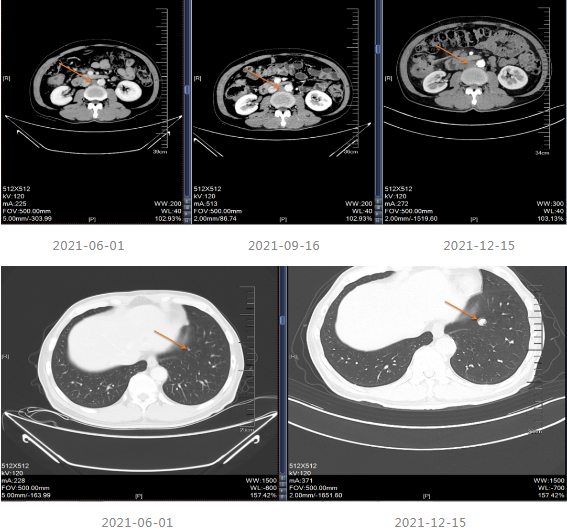

2021.06-01复查影像学提示肝胃间隙及腹膜后淋巴结较前增大,疗效评价PD。

2021-06-08至2021-12-11采用“贝伐珠单抗+Cap”治疗8个周期。

2021-12-15影像学复查提示疾病进展。